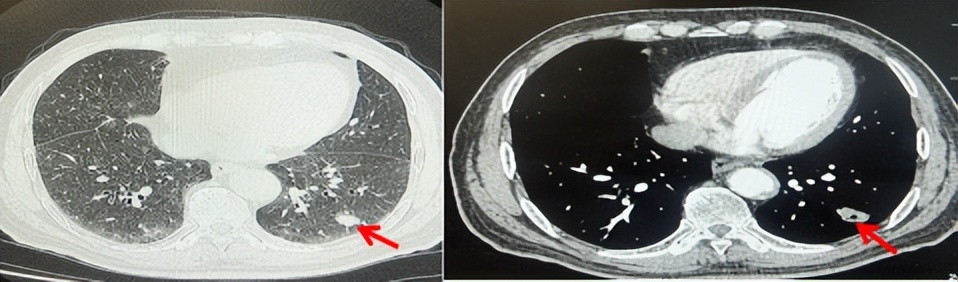

2024.09.12复查胸部CT示左侧胸膜结节,大者约为27mmx13mm,考虑转移可能性大,纵隔淋巴结增大,恶性?(如图6)。患者行胸膜穿刺活检取病理,结果示(胸膜)结合免疫组化,支持鳞状细胞癌,PD-L1(克隆号28-8)TPS约20%。分期为rT0N2bM1a IVA期,DFS为10个月。2024.09.24起行替雷利珠单抗联合紫杉醇+卡铂方案治疗4周期,复查胸CT评效SD(如图7)。后患者因脑梗塞停止治疗,于综合医院就诊,后未返院复查及治疗。

图6:患者胸膜及纵隔转移(2024.09)胸部CT肺窗及纵隔窗